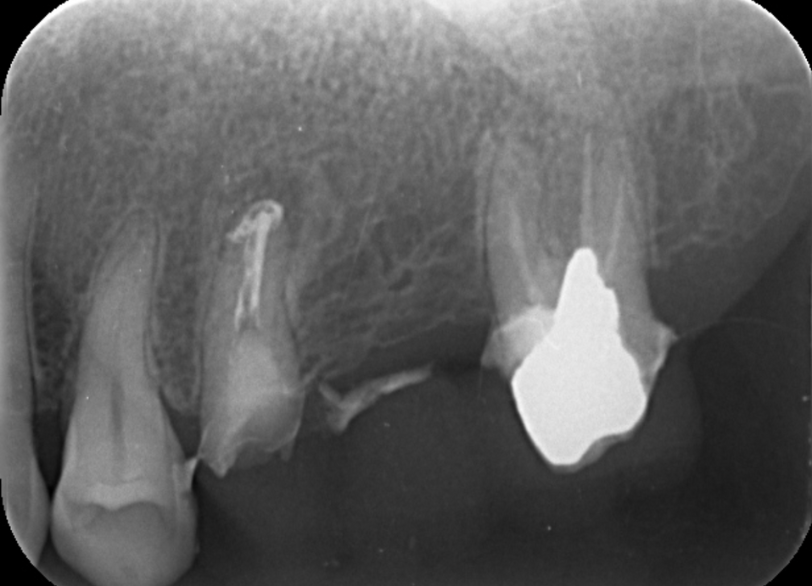

⑥セラミックに置き換えるため虫歯を除きレントゲンにて確実な精査を行った

| 診断 | ①下顎両側臼歯欠損 ②上顎左側5根尖性歯周炎 ③上顎左側6欠損 ④上顎右側4歯根破折 ⑤上顎右側567欠損 ⑥上顎左側7う蝕 ⑦上顎右側7う蝕 |

| 処置内容 (または主訴) | ①義歯 ②顕微鏡を用いた感染根管治療 ③インプラント治療 ④抜歯→骨造成→インプラント ⑤インプラント治療 ⑥セラミックによる被せ物の修復 ⑦セラミックによる被せ物の修復 |